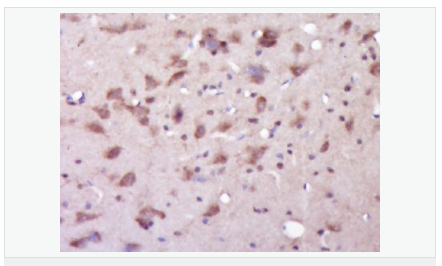

| 產(chǎn)品應用 | WB=1:500-2000 ELISA=1:5000-10000 IHC-P=1:100-500 IHC-F=1:100-500 Flow-Cyt=1ug/test IF=1:100-500 (石蠟切片需做抗原修復) not yet tested in other applications. optimal dilutions/concentrations should be determined by the end user. |

| 產(chǎn)品介紹 | Alzheimer's disease (AD) patients with an inherited form of the disease carry mutations in the presenilin proteins (PSEN1; PSEN2) or in the amyloid precursor protein (APP). These disease-linked mutations result in increased production of the longer form of amyloid-beta (main component of amyloid deposits found in AD brains). Presenilins are postulated to regulate APP processing through their effects on gamma-secretase, an enzyme that cleaves APP. Also, it is thought that the presenilins are involved in the cleavage of the Notch receptor, such that they either directly regulate gamma-secretase activity or themselves are protease enzymes. Several alternatively spliced transcript variants encoding different isoforms have been identified for this gene, the full-length nature of only some have been determined. [provided by RefSeq, Aug 2008] Function: Probable catalytic subunit of the gamma-secretase complex, an endoprotease complex that catalyzes the intramembrane cleavage of integral membrane proteins such as Notch receptors and APP (beta-amyloid precursor protein). Requires the other members of the gamma-secretase complex to have a protease activity. May play a role in intracellular signaling and gene expression or in linking chromatin to the nuclear membrane. Stimulates cell-cell adhesion though its association with the E-cadherin/catenin complex. Under conditions of apoptosis or calcium influx, cleaves E-cadherin promoting the disassembly of the E-cadherin/catenin complex and increasing the pool of cytoplasmic beta-catenin, thus negatively regulating Wnt signaling. May also play a role in hematopoiesis. Subunit: Homodimer. Component of the gamma-secretase complex, a complex composed of a presenilin homodimer (PSEN1 or PSEN2), nicastrin (NCSTN), APH1 (APH1A or APH1B) and PEN2. Such minimal complex is sufficient for secretase activity. Other components which are associated with the complex include SLC25A64, SLC5A7, PHB and PSEN1 isoform 3. Predominantly heterodimer of a N-terminal (NTF) and a C-terminal (CTF) endoproteolytical fragment. Associates with proteolytic processed C-terminal fragments C83 and C99 of the amyloid precursor protein (APP). Associates with NOTCH1. Associates with cadherin/catenin adhesion complexes through direct binding to CDH1 or CDH2. Interaction with CDH1 stabilizes the complex and stimulates cell-cell aggregation. Interaction with CDH2 is essential for trafficking of CDH2 from the endoplasmic reticulum to the plasma membrane. Interacts with CTNND2, CTNNB1, HERPUD1, FLNA, FLNB, MTCH1, PKP4 and PARL. Interacts through its N-terminus with isoform 3 of GFAP. Interacts with DOCK3. Subcellular Location: Endoplasmic reticulum membrane; Multi-pass membrane protein. Golgi apparatus membrane; Multi-pass membrane protein. Cell surface. Note=Bound to NOTCH1 also at the cell surface. Colocalizes with CDH1/2 at sites of cell-cell contact. Colocalizes with CTNNB1 in the endoplasmic reticulum and the proximity of the plasma membrane. Also present in azurophil granules of neutrophils. Tissue Specificity: Expressed in a wide range of tissues including various regions of the brain, liver, spleen and lymph nodes. Post-translational modifications: Heterogeneous proteolytic processing generates N-terminal (NTF) and C-terminal (CTF) fragments of approximately 35 and 20 kDa, respectively. During apoptosis, the C-terminal fragment (CTF) is further cleaved by caspase-3 to produce the fragment, PS1-CTF12. After endoproteolysis, the C-terminal fragment (CTF) is phosphorylated on serine residues by PKA and/or PKC. Phosphorylation on Ser-346 inhibits endoproteolysis. DISEASE: Defects in PSEN1 are a cause of Alzheimer disease type 3 (AD3) [MIM:607822]. AD3 is a familial early-onset form of Alzheimer disease. Alzheimer disease is a neurodegenerative disorder characterized by progressive dementia, loss of cognitive abilities, and deposition of fibrillar amyloid proteins as intraneuronal neurofibrillary tangles, extracellular amyloid plaques and vascular amyloid deposits. The major constituent of these plaques is the neurotoxic amyloid-beta-APP 40-42 peptide (s), derived proteolytically from the transmembrane precursor protein APP by sequential secretase processing. The cytotoxic C-terminal fragments (CTFs) and the caspase-cleaved products such as C31 derived from APP, are also implicated in neuronal death. Defects in PSEN1 are a cause of frontotemporal dementia (FTD) [MIM:600274]. Similarity: Belongs to the peptidase A22A family. SWISS: P49768 Gene ID: 5663 Database links: Entrez Gene: 5663 Human Entrez Gene: 19164 Mouse Omim: 104311 Human SwissProt: P49768 Human SwissProt: P49769 Mouse Unigene: 3260 Human Unigene: 998 Mouse Unigene: 44440 Rat Important Note: This product as supplied is intended for research use only, not for use in human, therapeutic or diagnostic applications. 此抗體識別分子量為45-50kDa早老素蛋白-1。PS-1主要在神經(jīng)細胞中表達,早老蛋白集中于體細胞和樹突狀細胞中。相反,再早發(fā)家族AD(FAD)中和散發(fā)AD病人中,PS1免疫反應出現(xiàn)在老年斑和神經(jīng)纖維纏結的神經(jīng)炎中。 |